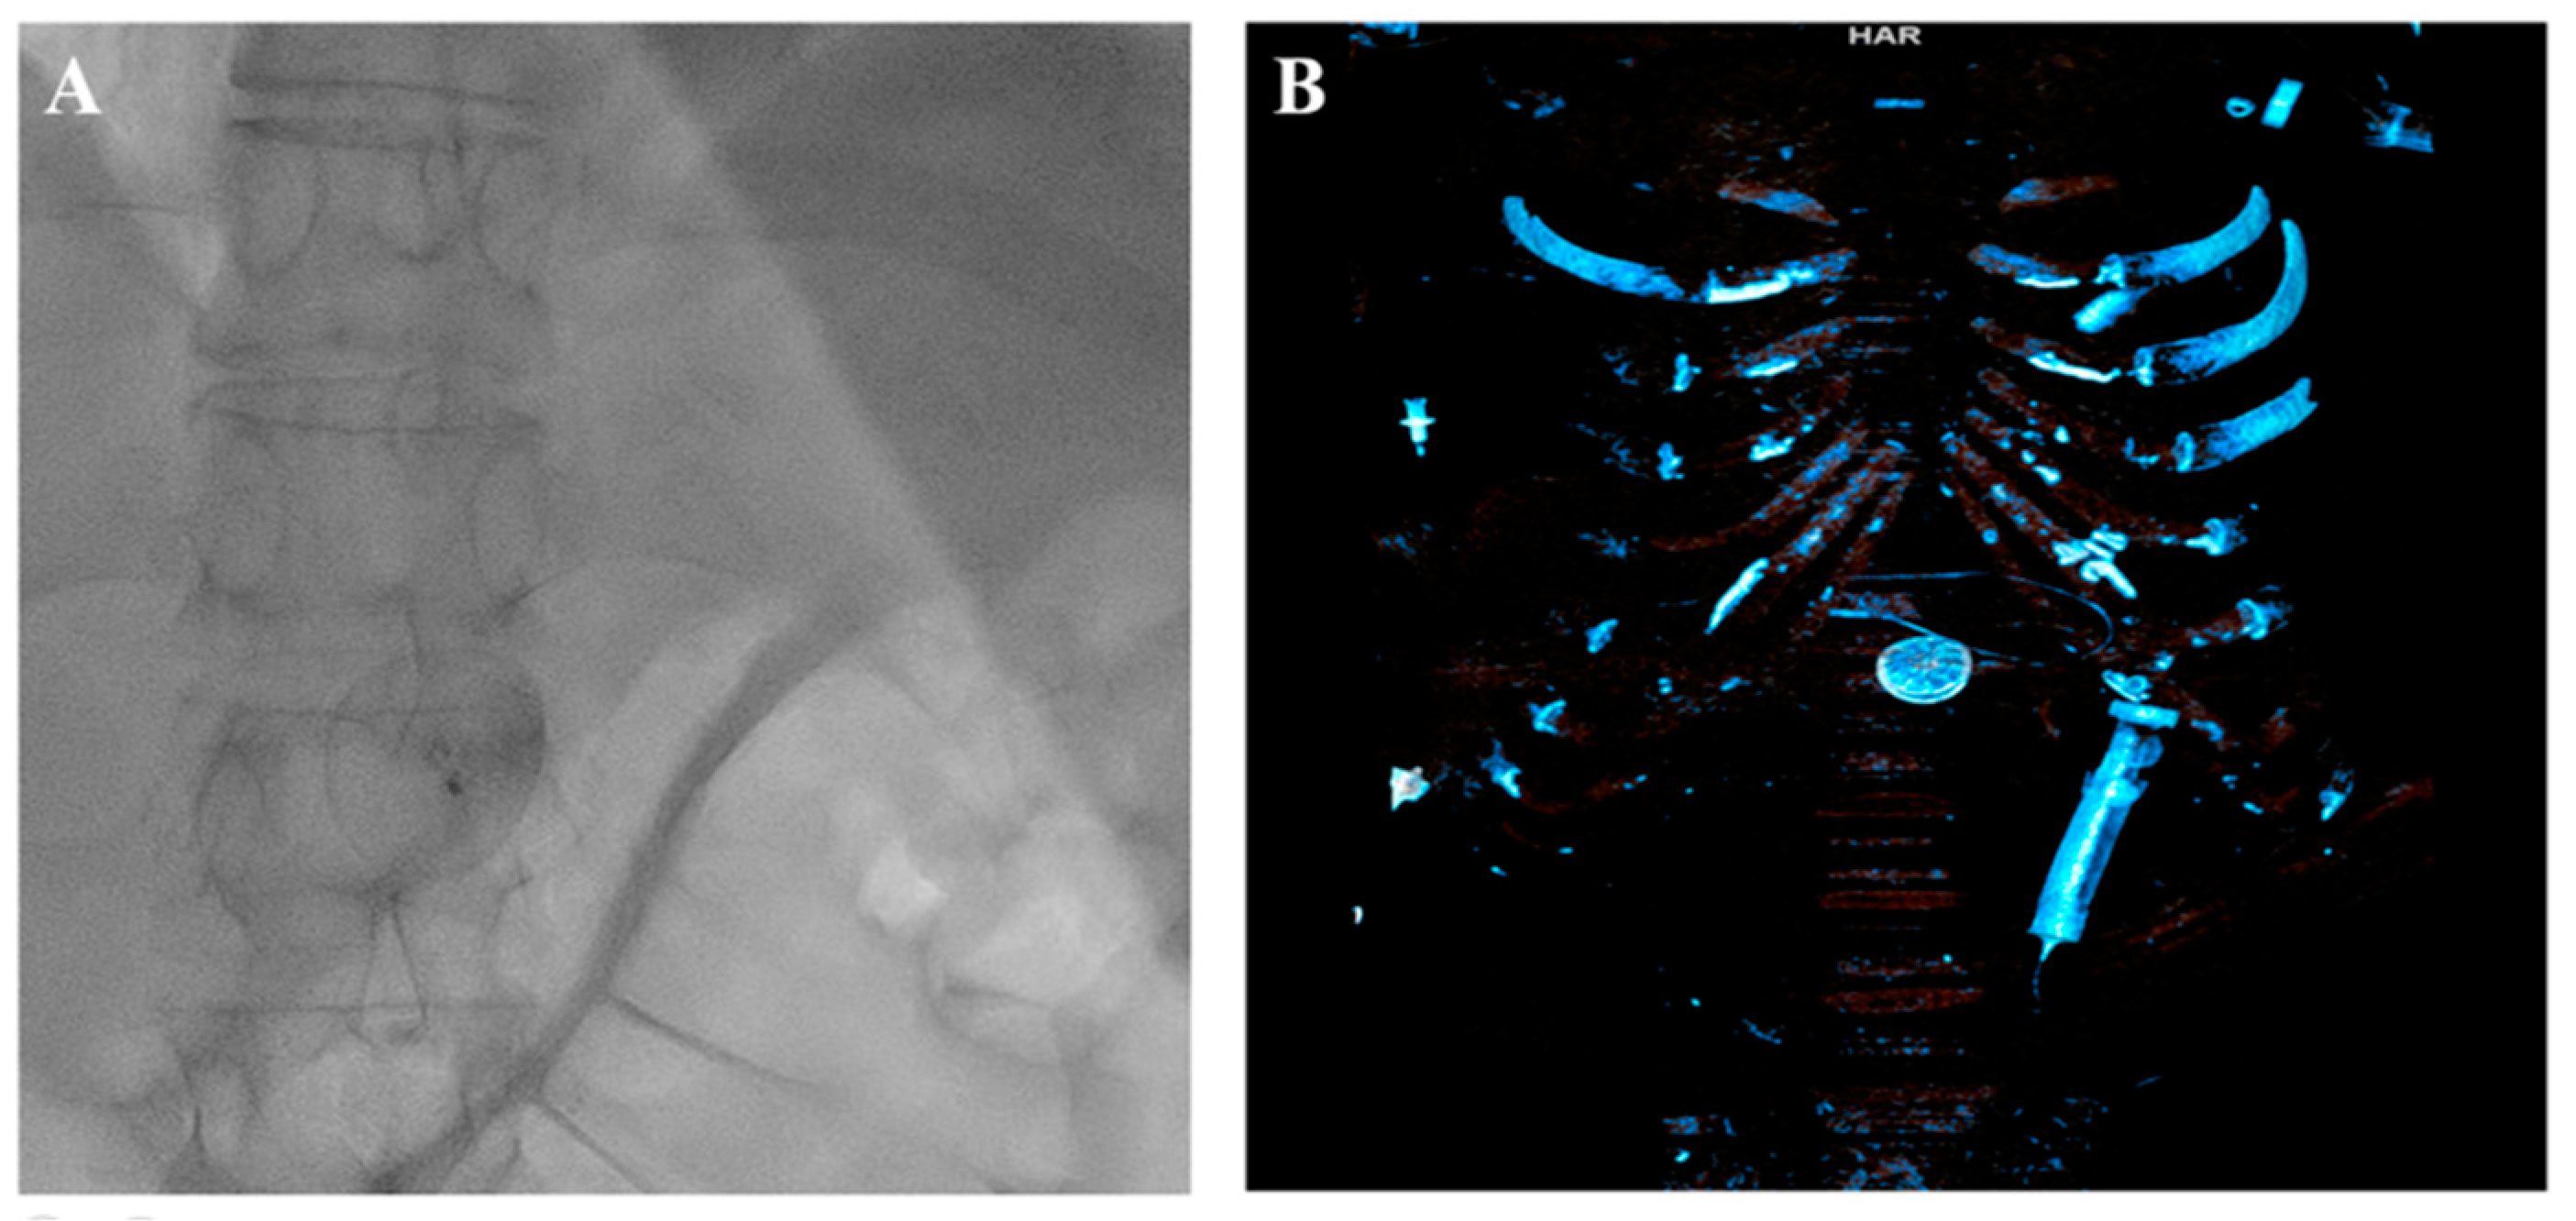

Therefore, in response to the notably aneurysmatic, floppy, and thin interatrial septum, to prevent the unintended slippage of the PFO closure device, we undertook efforts to reposition the occluder to stabilize a large portion of the septum despite recognizing that this might have necessitated the use of a larger device. Following this adjustment, the PFO occluder was unexpectedly and unintentionally detached, without the release of the device safety mechanism. Initially, the position of the PFO occluder was confirmed on the radiogram in the projection of the left atrium (LA) and then in the left ventricle (LV) projection (Figure 3).

Figure 3.

Detached occluder in the projection of the left ventricle. (A) Fluoroscopy. (B) Transthoracic echocardiography.

The attempts to snare it from the LA and LV were unsuccessful. Furthermore, the device promptly migrated to the abdominal aorta, located below the diaphragm at the junction of the truncus coeliacus, which was confirmed via a CT scan (Figure 4).

Figure 4.

Occluder in the abdominal aorta. (A) Fluoroscopy. (B) Computed tomography.